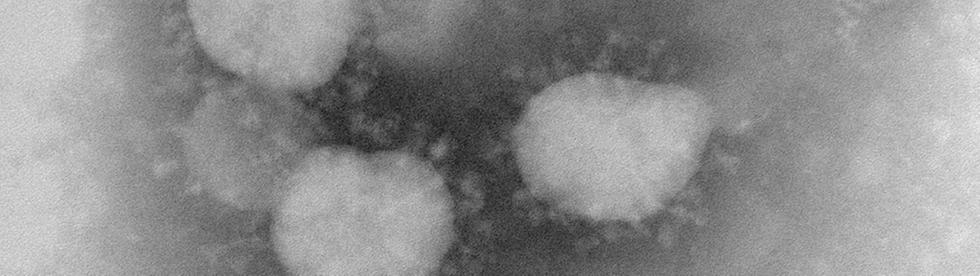

Primarul Călin Bibarț a anunțat astăzi 23.03 printr-un video live pe pagina sa de Facebook faptul că avem prima persoană confirmată cu COVID-19 în municipiul Arad.